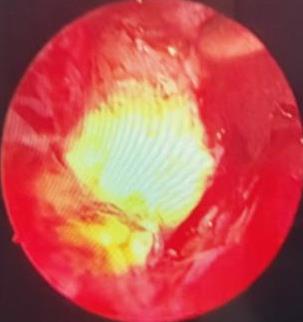

• 内镜诊断和治疗十二指肠黏膜下恒径动脉破裂出血并活动性出血的价值(附6例报告)

2026, 32(1):80-83. DOI: 10.12235/E20250357

摘要 (39) HTML (37) PDF 1.21 M (63) 评论 (0) 收藏

摘要:目的 探讨内镜诊断和治疗十二指肠黏膜下恒径动脉破裂出血并活动性出血的价值。方法 回顾性分析2015年6月-2023年1月该院经内镜确诊十二指肠黏膜下恒径动脉破裂出血并活动性出血的6例患者的临床资料。总结临床表现、内镜下特征和治疗转归。结果 于24 h内完成急诊内镜检查,证实6例均为单纯十二指肠黏膜下恒径动脉破裂出血,并成功行内镜下钛夹止血治疗。结论 内镜诊断十二指肠黏膜下恒径动脉破裂出血所致的大出血,具有较高的价值。此外,于内镜下及时采取积极、有效的干预措施,可快速止血,降低死亡率。值得应用于临床。